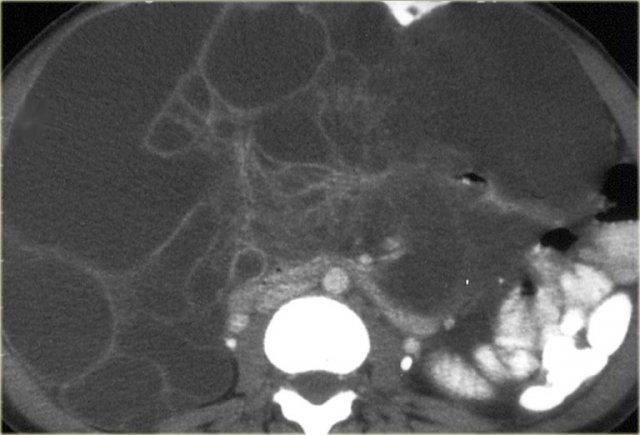

Giả U Nhầy Phúc Mạc

Giả u nhầy phúc mạc là hậu quả của ung thư biểu mô tuyến nhầy của ruột thừa, biểu hiện dưới dạng nang nhầy (mucocele) và lan rộng vào khoang phúc mạc.

Đây là một hội chứng lâm sàng, đặc trưng bởi tình trạng cổ trướng nhầy thể tích lớn, tái phát và khó điều trị, do sự phát triển trên bề mặt phúc mạc mà không xâm lấn đáng kể vào các mô bên dưới.

Đặc điểm điển hình của giả u nhầy phúc mạc là hình ảnh lõm múi trên bề mặt gan và lách.

Khác với di căn phúc mạc, không có các nốt khối u.

Có thể có một số vôi hóa.